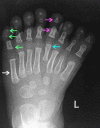

Mirror foot is a rare abnormality which presents as a preaxial, postaxial, or central polydactyly of the foot. The latter is encountered infrequently. We describe the case of a central mirror foot. Our patient had eight digits of a central ray pattern type with fully developed metatarsal, proximal, middle, and distal phalanges, as well as a medial toe syndactyly. He had no tarsal bone duplications. He was treated by central ray resection via double V-shaped incisions on the dorsal and plantar aspects of the foot, while preserving the medial and lateral rays. The results were satisfactory. We describe the technique and attempt a review of the literature.